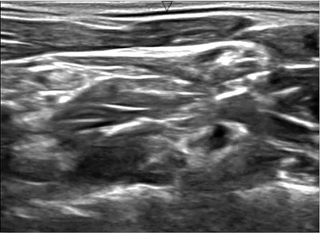

목 초음파 이미지에서 신경부위 세그멘테이션을 하는 모델을 만드는 것과 모델의 성능(정확도)을 향상시키기 위해 여러가지 환경을 변화시키면서 이를 연구하는 것.

실제 환자 초음파 이미지 학습을 통해 얻은 마스킹 이미지